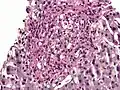

PAS diastase showing Histoplasma in a liver biopsy.

Periodic acid–Schiff–diastase (PAS-D, PAS diastase) stain is a periodic acid–Schiff (PAS) stain used in combination with diastase, an enzyme that breaks down glycogen. PAS-D is a stain often used by pathologists as an ancillary study in making a histologic diagnosis on paraffin-embedded tissue specimens. PAS stain typically gives a magenta color in the presence of glycogen. When PAS and diastase are used together, a light pink color replaces the deep magenta. Differences in the intensities of the two stains (PAS and PAS-D) can be attributed to different glycogen concentrations and can be used to semiquantify glycogen in samples. In practice, the tissue is deparaffinized, the diastase incubates, and the PAS stain is applied.